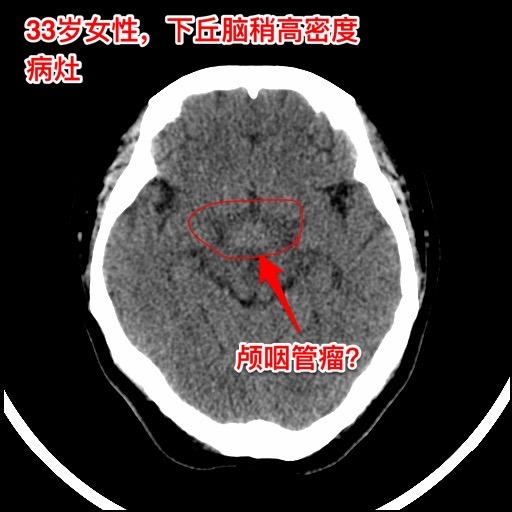

年轻女子四年体重从120斤增到220斤。河北石家庄地区33岁女性,四年前(29岁)开始出现问题,内分泌紊乱(生理周期停了)、多饮多尿,贪食,总爱吃东西,体重稳步增长,四年时间从120斤增长到220斤! 而且还出现多睡,一天到晚躺下就想睡觉。近期还出现记忆力差、头脑糊涂。自从四年前发病后就不能工作了。 2024年12月15日外院的磁共振检查发现下丘脑病变,怀疑是颅咽管瘤。 患者的弟弟找到我,希望我能为他的姐姐解除病痛。 经过仔细分析病人的影像学资